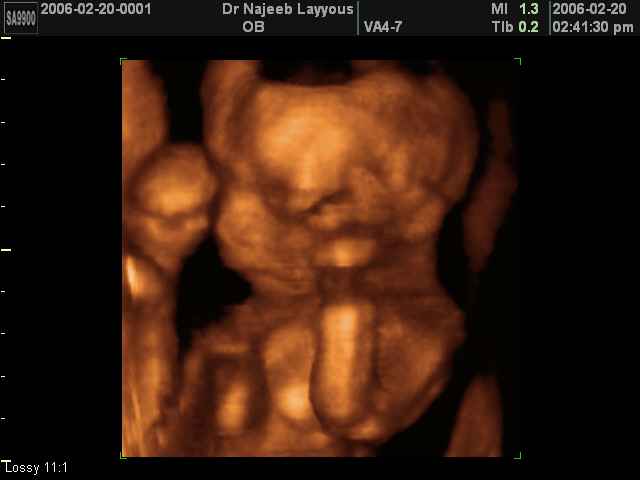

صور لتصرفات الجنين داخل الرحم بجهاز الالتراساوند ثلاثي الأبعاد | الدكتور نجيب ليوس

صور بجهاز الموجات فوق صوتية ثلاثي الأبعاد لتصرفات الجنين داخل الرحم